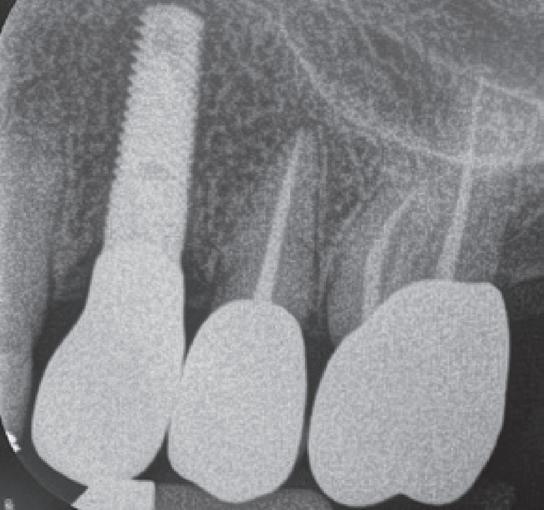

– 5 cavity classes